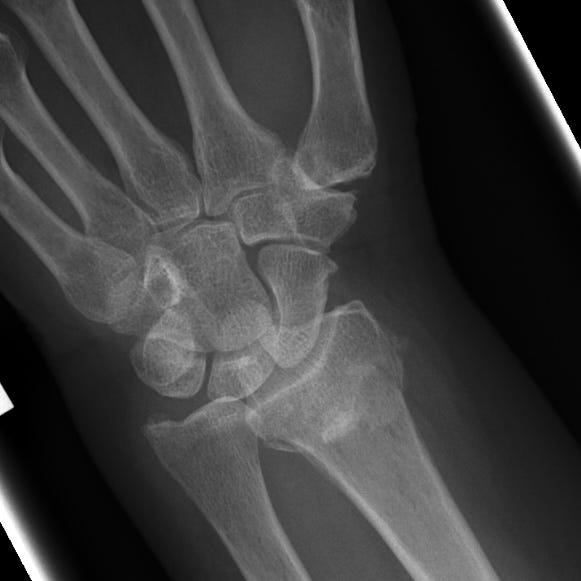

Distal Radial Fractures Pdf Skeletal System Musculoskeletal Distal radius fractures are classified according to (1) extension into the radiocarpal joint, (2) extension to the distal radioulnar articulation, and (3) the presence of an associated ulnar styloid fracture. Distal radius fractures are the most common orthopaedic injury and generally result from fall on an outstretched hand.

Distal Radial Fractures By Alexander Baxter Radnotes Acute distal radius fracture results in pain, tenderness, swelling and potential deformity. patients may be faced with substantial morbidity if fracture healing is delayed or results in clinically significant deformity. Distal radius fractures, commonly known as a wrist fracture, are defined by the involvement of the metaphysis of the distal radius. in younger patients, they are commonly associated with high energy mechanisms, and in older patients, they more frequently occur with lower energy mechanisms or falls. Common distal radial fractures home uw emergency radiology trauma radiology reference resource 09. upper extremity common distal radial fractures page views: 15,253. In this report, we have summarized the evidence on treatment and rehabilitation of distal radial fractures from the most recent available systematic reviews of high quality.

Distal Radial Fractures By Alexander Baxter Radnotes Common distal radial fractures home uw emergency radiology trauma radiology reference resource 09. upper extremity common distal radial fractures page views: 15,253. In this report, we have summarized the evidence on treatment and rehabilitation of distal radial fractures from the most recent available systematic reviews of high quality. Distal radial fractures are a heterogeneous group of fractures that occur at the distal radius and are the dominant fracture type at the wrist. these common fractures usually occur when significant force is applied to the distal radial metaphysis. A randomized, controlled trial of distal radius fractures with metaphyseal displacement but without joint incongruity: closed reduction and casting versus closed reduction, spanning external fixation, and optional percutaneous k wires. We review the evidence behind each guideline and highlight the practical implications of each guideline on care. This guideline is based upon 6 high quality studies, with 3 comparing different fixation techniques for complete intra articular distal radius fractures (jakubietz, yazdanshenas, hammer) and 3 comparing different fixation techniques for unstable distal radius fractures (marcheix, rozental, goehre).